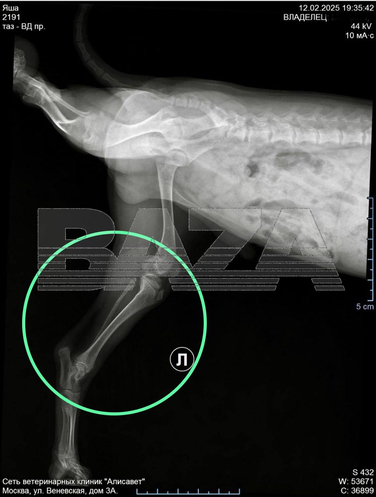

Хозяйка показала щенка ветеринарам, которые установили, что у него перелом малой берцовой кости. Конечность животному сломала грумер во время процедур.

Фото: Telegram / BAZA